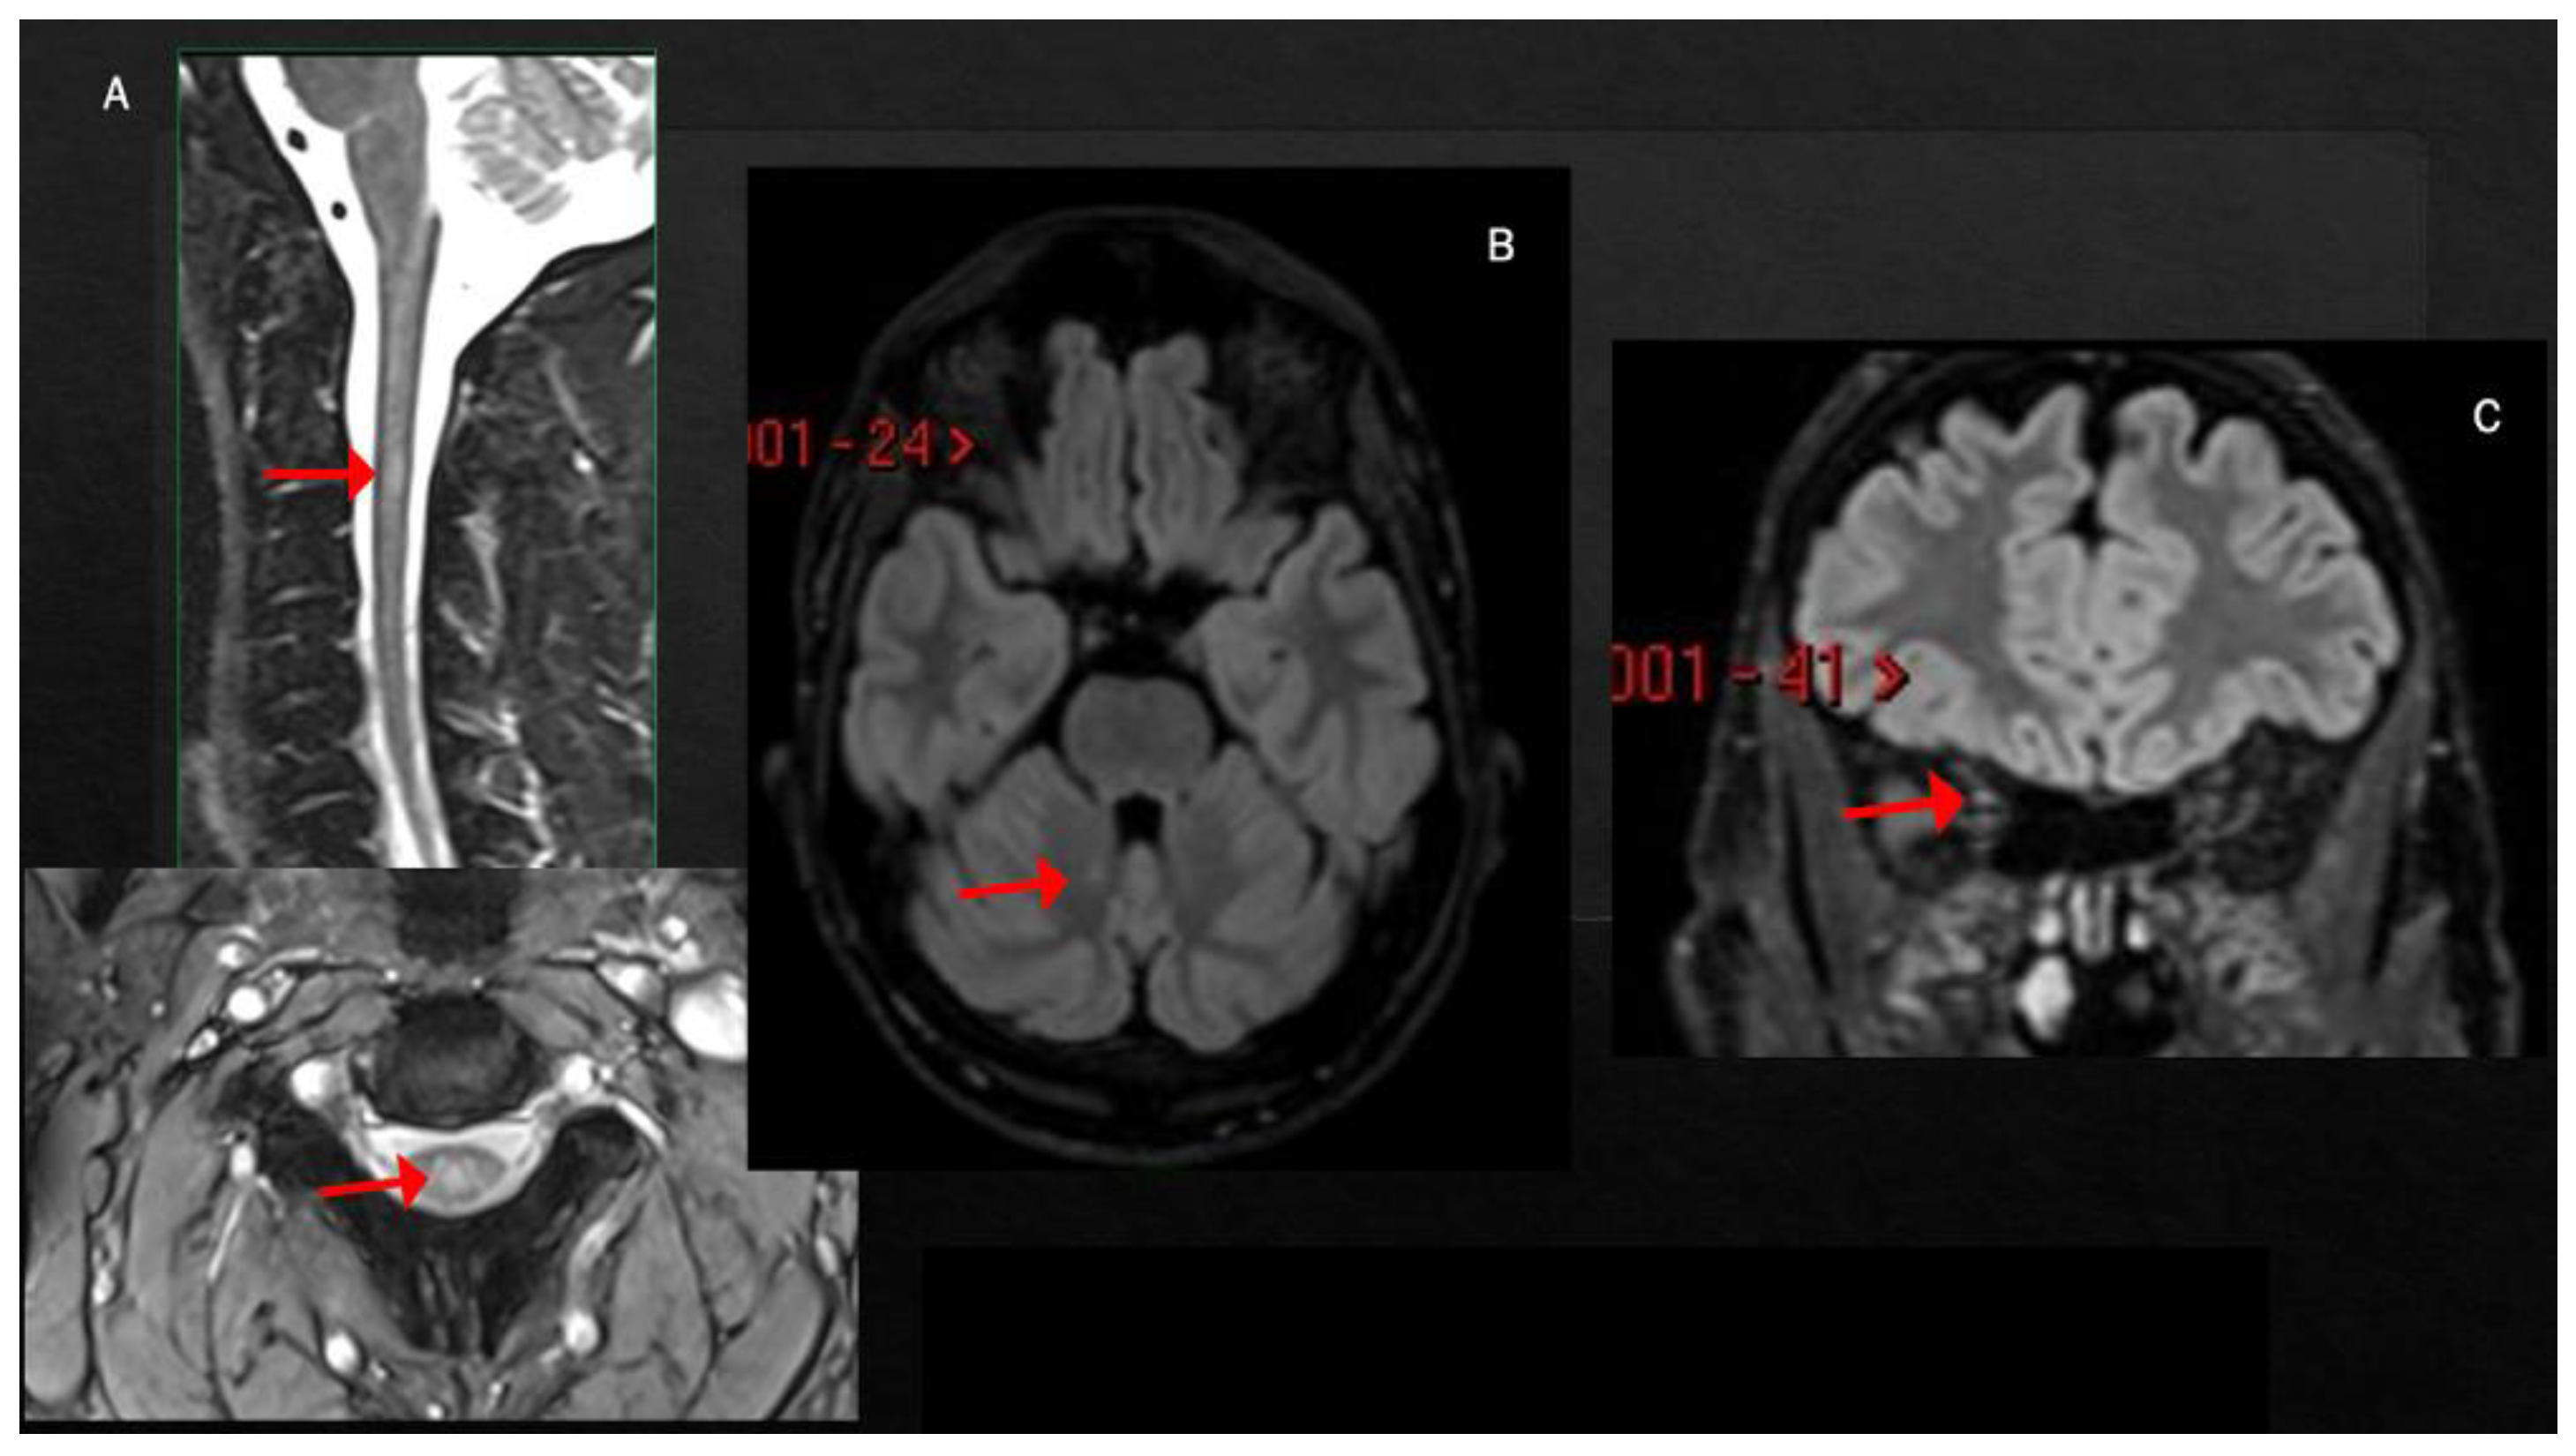

3. MS Relapses after COVID-19 Infection

| MS RELAPSE | |||||||

| Pignolo et al. [55] 2nd case | 2 months | Uncertain (unilateral motor symptoms) | ST | + | + | - | NA |

| $ Case 5 | 3 weeks | Cerebellum (trunk/gait ataxia, dysmetria) | NA | NA | NA | + | NA |

| Finsterer [61] | 2 weeks | SC (sensory symptoms both inferior limbs and trunk level) | SC | + | + | - | NA |